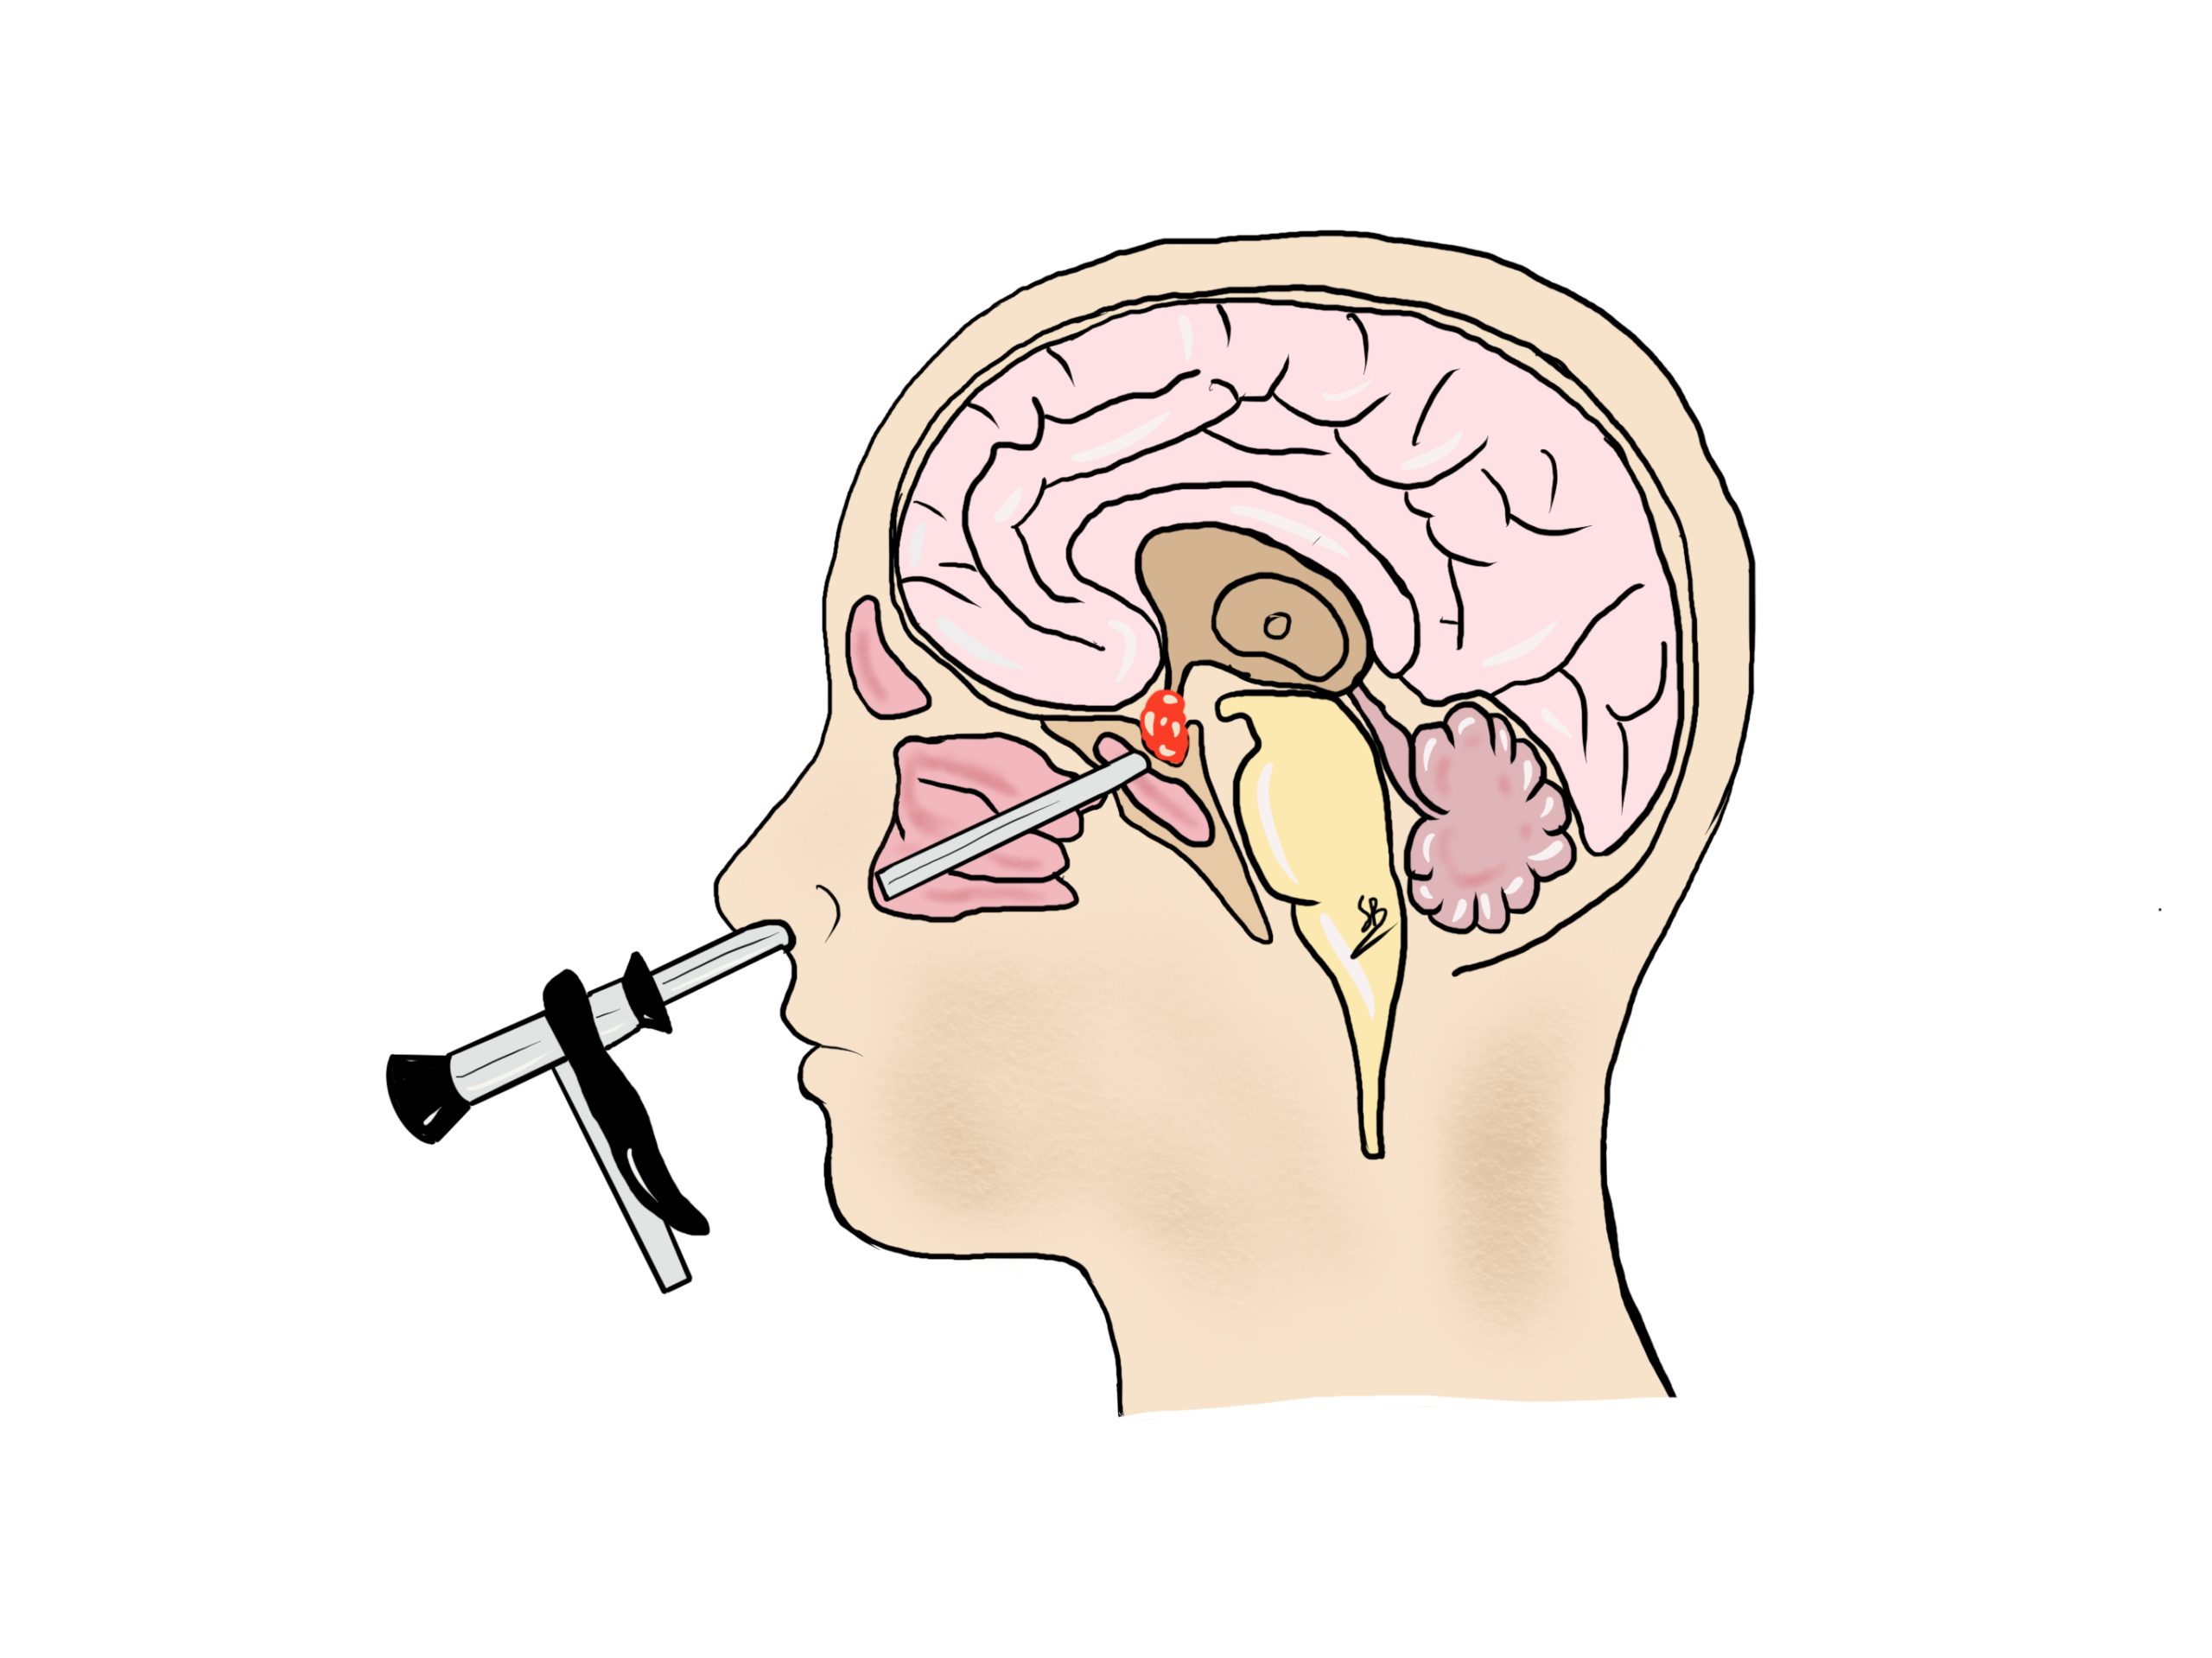

La chirurgia dell’ipofisi è una chirurgia realizzata con l’ausilio di un endoscopio di 5 mm di diametro introdotto nel naso dentro il seno sfenoidale. Dopo avere fresato l’osso della base cranica di qualche millimetro, il tumore ipofisario è asportato in maniera accurata. Il Dr. Robert e la Dr.ssa Bonasia presentano una grande esperienza per questo tipo di chirurgia con più di 100 interventi all’ipofisi. L’intervento viene fatta alla Clinique La Source di Losanna.

Approccio trans-nasale